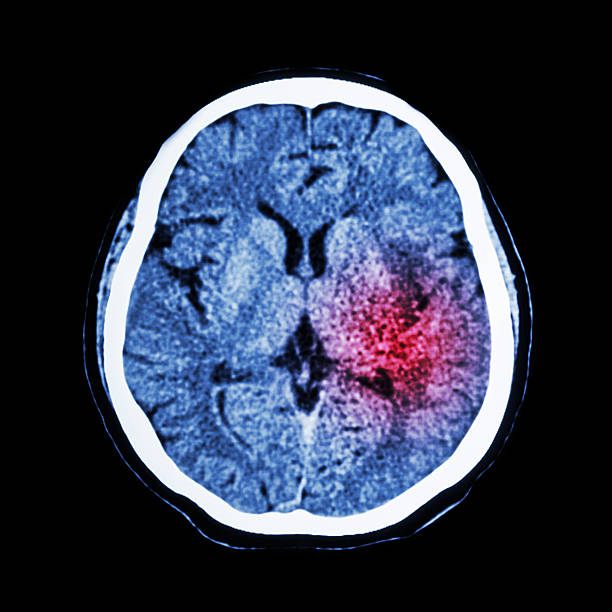

뇌출혈은 뇌안에 있는 혈관에서 출혈이 발생하여 뇌조직이 손상을 입는 질환이며, 중증의 뇌혈관질환 중 하나입니다. 일반적으로 고혈압, 동맥류, 혈관 기형, 혈전 등의 이유로 혈관이 파열하거나 뚫리면서 발생합니다.

뇌출혈은 갑작스러운 발작, 의식 잃음, 경련, 혼란, 언어 장애, 편마비 등의 증상을 일으키며, 이러한 증상이 발생하면 즉시 의료진의 진료를 받아야 합니다. 뇌출혈은 치료가 지연되면 심각한 후유증을 일으킬 수 있으므로, 조기 발견과 적절한 치료가 필요하기 때문에 이번 시간에는 뇌출혈 전조 증상에 대해 자세히 알아보겠습니다.